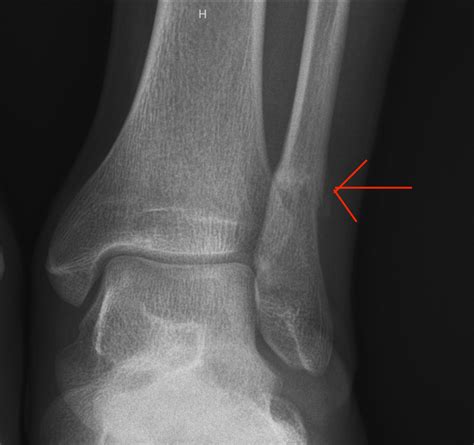

The fibula is the thin, long bone located on the lateral (outer) side of the lower leg. While it does not bear the majority of your body weight—the tibia carries most of it—the fibula serves as a crucial anchor point for various muscles that control ankle stability and foot movement. A Fibula Stress Fracture occurs when the bone is subjected to repeated force faster than it can remodel and repair itself. Over time, these tiny, microscopic cracks accumulate, leading to structural weakness.

• Point tenderness, where the pain is centralized in one specific spot along the fibula bone.

If you find that the pain persists for more than two weeks despite taking rest days, it is highly recommended to seek a professional medical evaluation, such as an X-ray or MRI, to confirm the diagnosis.